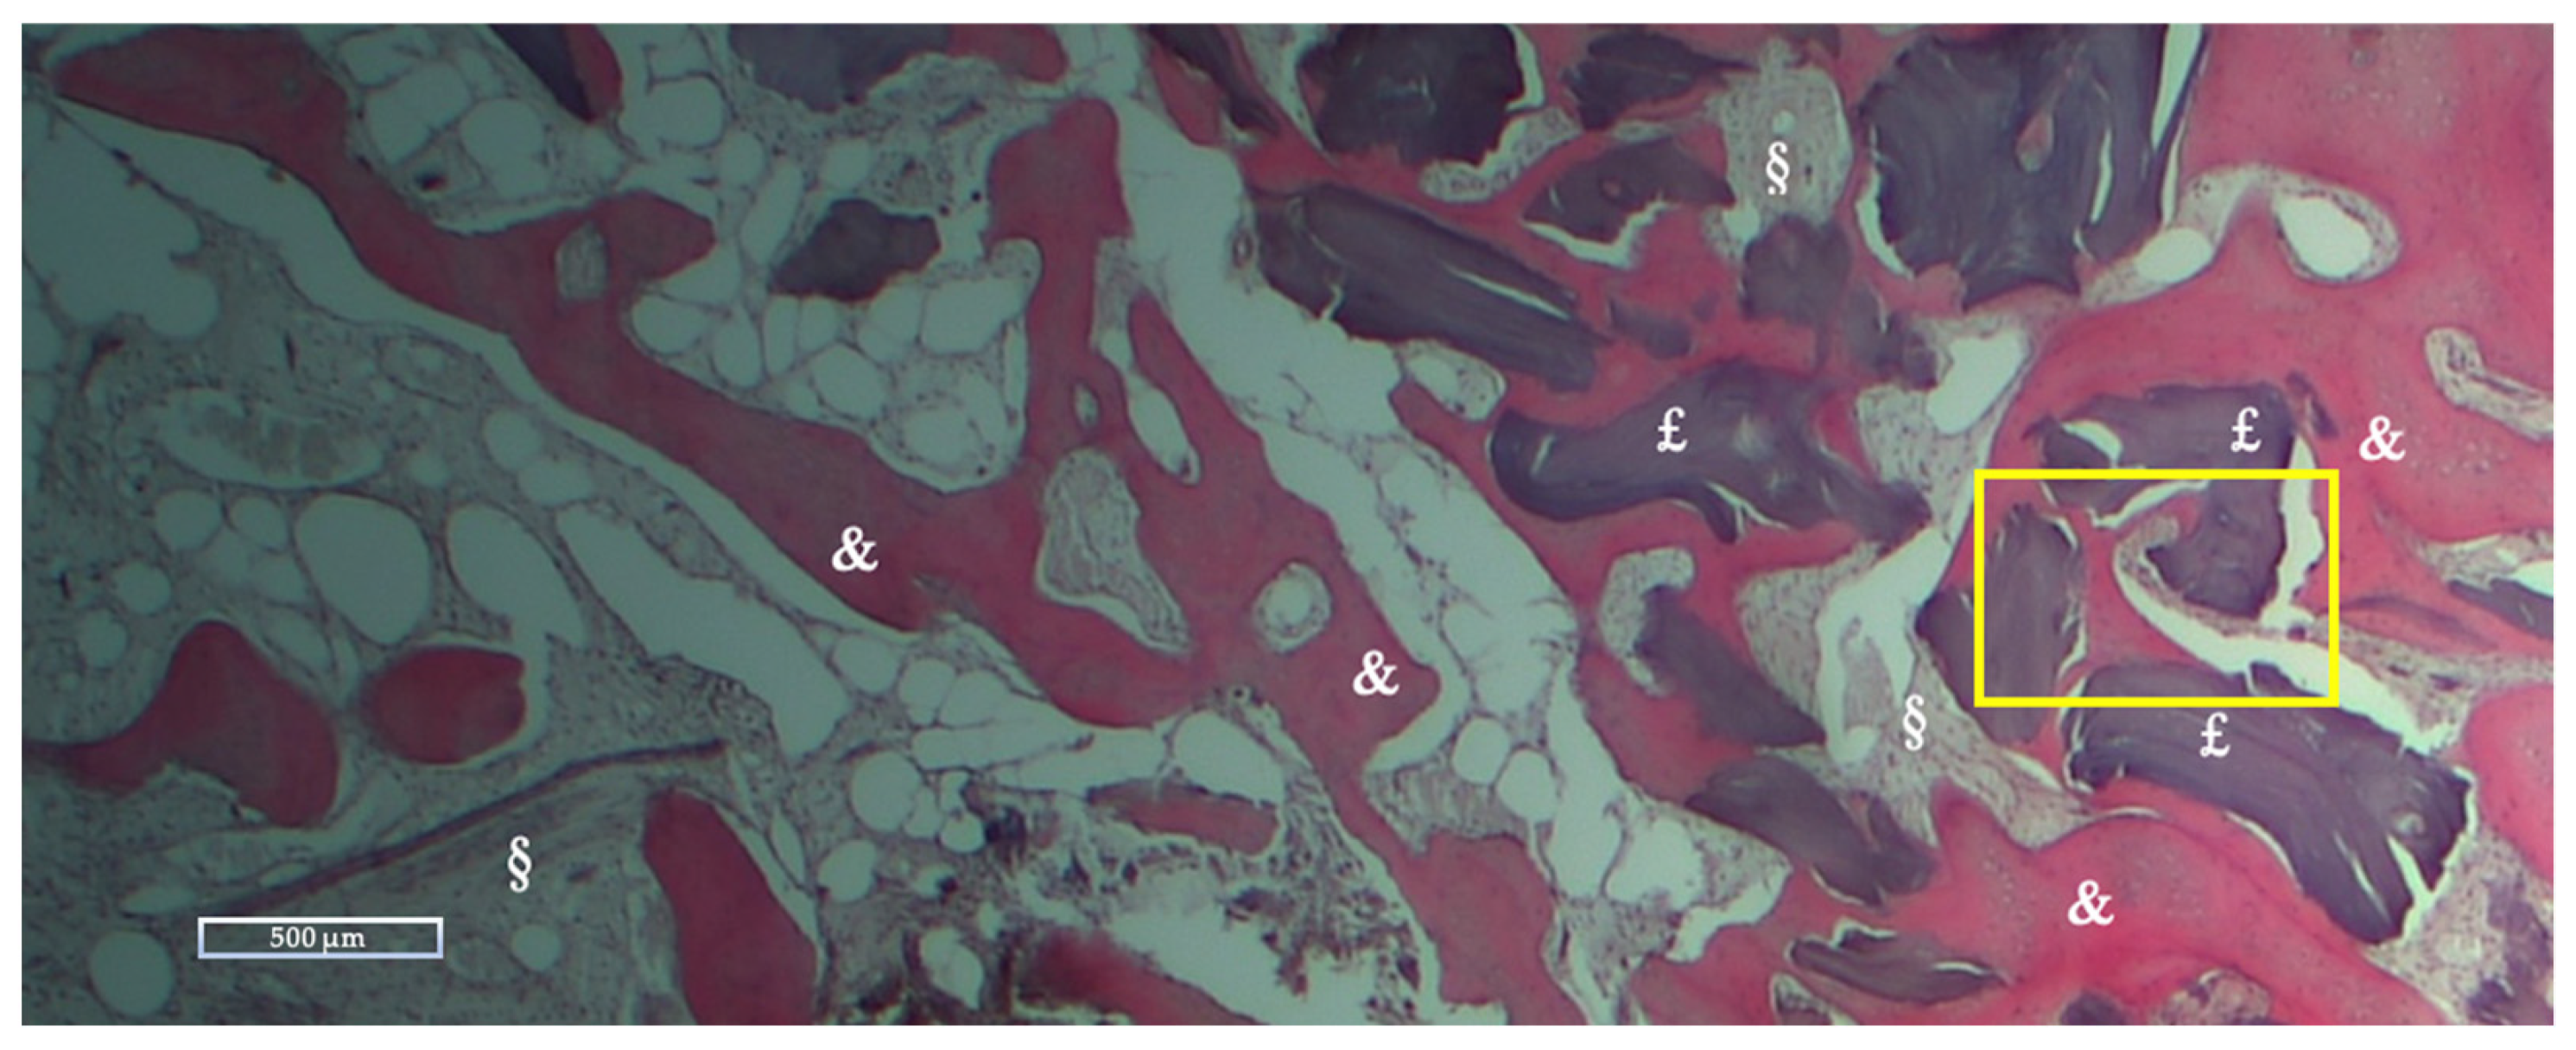

Histologic and Histomorphometric Results

| NFB | RB | SF | |

|---|---|---|---|

| Mean % ± Std dev | 28.27 ± 10.62 | 10.39 ± 12.01 | 61.33 ± 12.08 |

| Range % (Min-Max) | 16.51–59.74 | 0–36.89 | 40.26–75.59 |